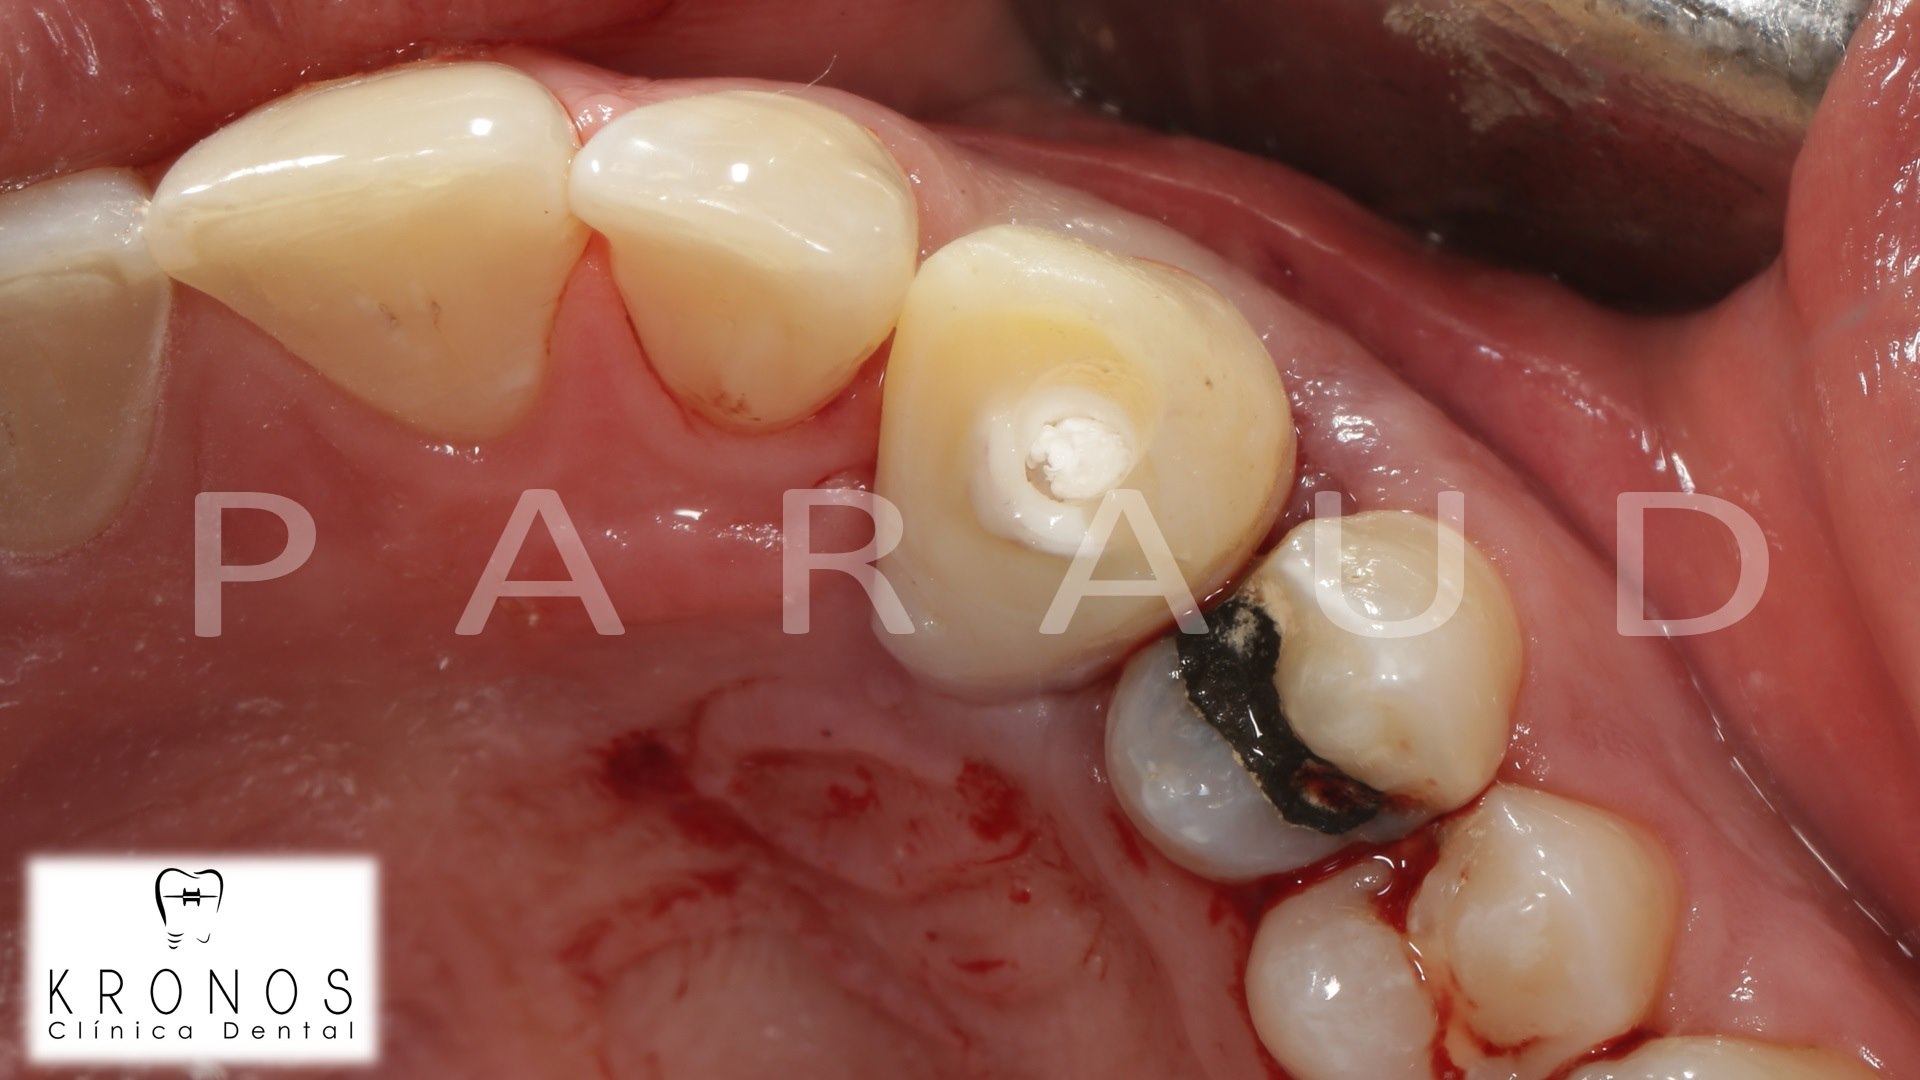

Clinical case: AnyRidge immediate loading

- Courtesy of Dr. Andres Paraud Freixas, Chile -

AnyRidge, ISQ value, initial stability, immediate loading, KnifeThread, maxillary anterior, Mega ISQ, Dr. Andres Paraud Freixas

AnyRidge implant system, Mega ISQ, Digital prosthesis